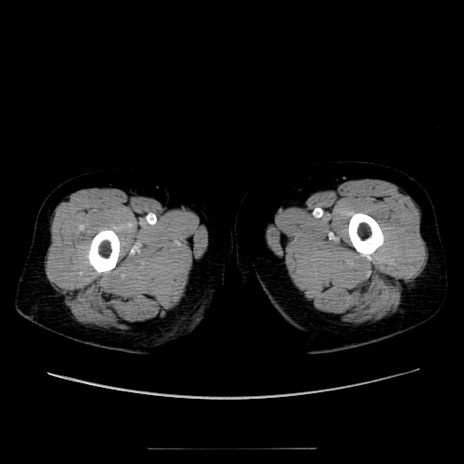

症例5(横断像)

【症例】70歳代女性

【主訴】お腹が張る

【現病歴】1週間くらい前から腹部膨満の自覚あり。昨日夜から増悪したため、本日救急外来受診。

【身体所見】意識清明、BT 36.5℃、BP 165/106mmHg、HR 80bpm、SpO2 98%、腹部:膨満、軟、自発痛・圧痛なし、触診にて不快感あり、腸蠕動音:減弱

【データ】WBC 12600、CRP 1.04